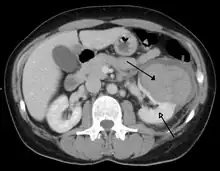

A large hematoma (closed arrow) of the left kidney (open arrow)

The kidneys may also be injured; they are somewhat but not completely protected by the ribs.[6] Kidney lacerations and contusions may also occur.[13] Kidney injury, a common finding in children with blunt abdominal trauma, may be associated with bloody urine.[13] Kidney lacerations may be associated with urinoma or leakage of urine into the abdomen.[4] A shattered kidney is one with multiple lacerations and an associated fragmentation of the kidney tissue.[4]